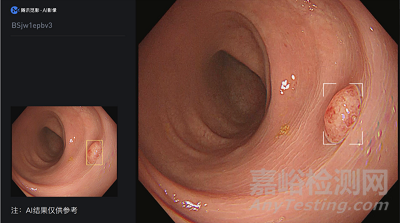

產(chǎn)品名稱:腸息肉電子下消化道內(nèi)窺鏡圖像輔助檢測(cè)軟件

生產(chǎn)企業(yè):武漢楚精靈醫(yī)療科技有限公司

批準(zhǔn)日期:2023-5-12

國(guó)械注準(zhǔn):20233210629

該產(chǎn)品在醫(yī)療機(jī)構(gòu)供執(zhí)業(yè)內(nèi)窺鏡醫(yī)師用于成人結(jié)腸內(nèi)窺鏡檢查時(shí),在內(nèi)窺鏡圖像處理器輸出的獨(dú)立視頻圖像中實(shí)時(shí)顯示疑似息肉的區(qū)域。

該產(chǎn)品為國(guó)內(nèi)首個(gè)利用深度學(xué)習(xí)技術(shù)同時(shí)進(jìn)行結(jié)直腸鏡檢查質(zhì)量控制和息肉輔助檢測(cè)的軟件。該產(chǎn)品與現(xiàn)有國(guó)內(nèi)外已上市同類產(chǎn)品相比,在識(shí)別息肉的同時(shí),采用深度學(xué)習(xí)技術(shù)、感知哈希算法等技術(shù)輔助醫(yī)生進(jìn)行操作控制,進(jìn)一步確保腸鏡檢查質(zhì)量,減少漏檢率,并提升檢查操作的規(guī)范性。

(僅作示意 )